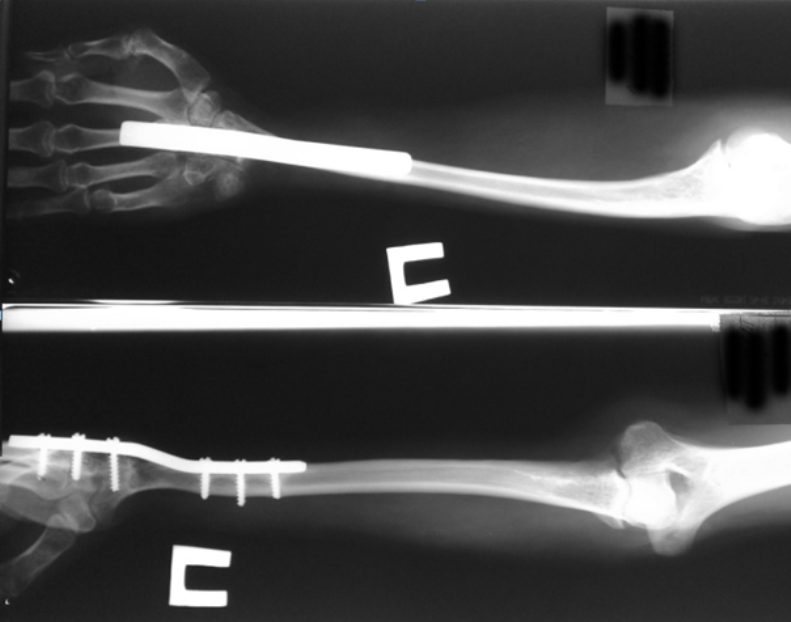

Радиоульнарный угол

Радиоульнарный угол 137 фото